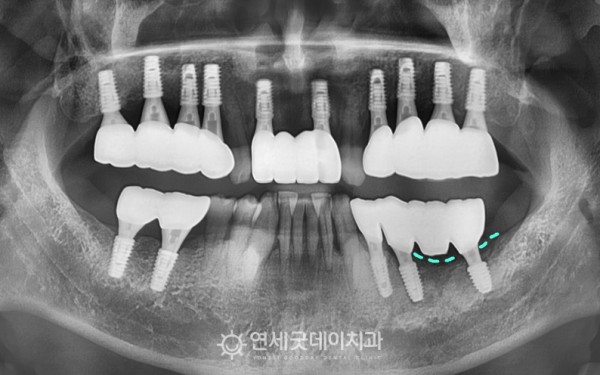

강원도에서 임플란트 재수술을 주소로

내원해주셨던 50대 남성 환자분입니다.

2년 전, 타원에서 전체적으로

임플란트 치료를 받으셨지만

#36,37 부위의 치조골 소실이 상당수 진행된 상태셨습니다.

엑스레이 상에서 #35 부위에

치근단 병소가 확인되었고,

이로 인해 #36,37 임플란트에

영향을 준 것으로 추정됐습니다.